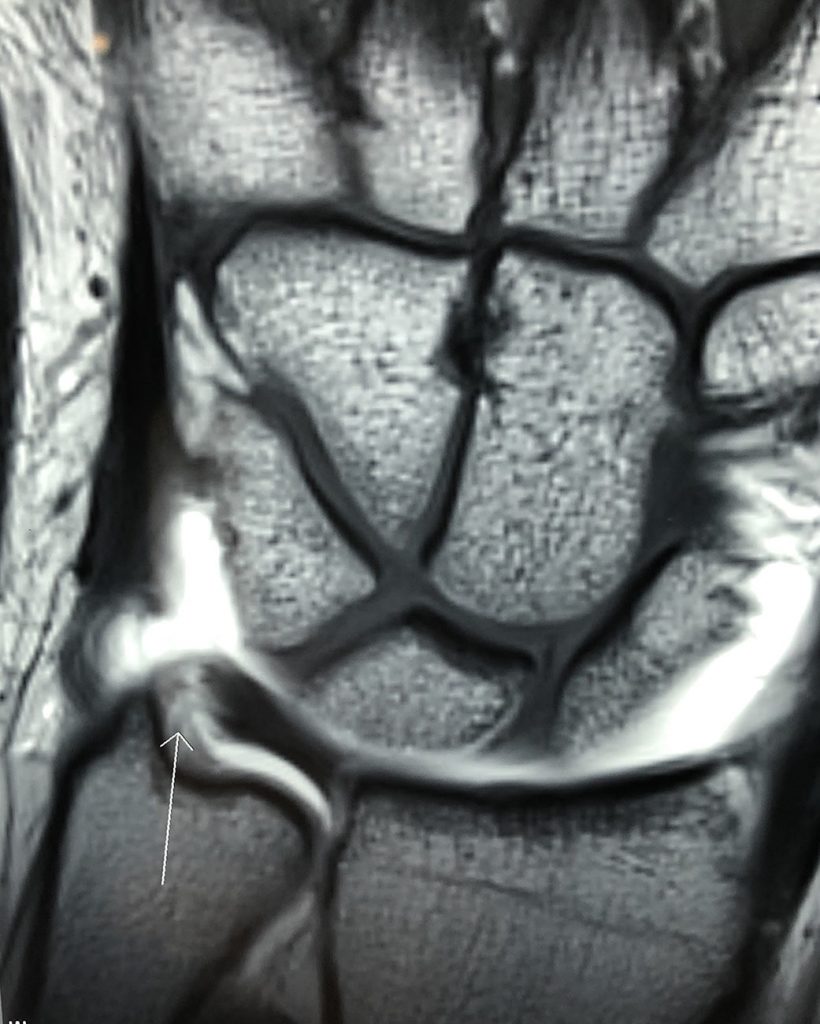

PATOLOGIAS MUÑECA - LESIÓN DEL COMPLEJO FIBROCARTÍLAGO TRIANGULAR (CFCT) Figura 2 - Lesión del Complejo Fibrocartílago Triangular

Figura 2 - Lesión del Complejo Fibrocartílago Triangular

Las lesiones del CFCT (Figura 2) suelen producirse en dos zonas diferentes y pueden ser causadas por diferentes problemas. El primer tipo de lesión se debe al desgaste natural, y el otro tipo generalmente se debe a un traumatismo agudo o traumatismos repetidos. Las lesiones debidas al desgaste son las más comunes y generalmente no se ven en personas jóvenes. Son más frecuentes a medida que uno envejece.